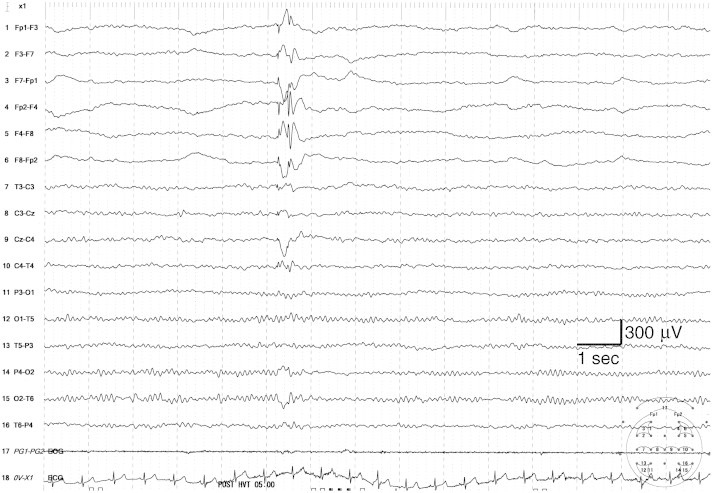

Fig. 1.

Ictal EEG recording during eyelid myoclonia shows 4- to 5-Hz generalized polyspike–waves preceded by focal frontal discharges.